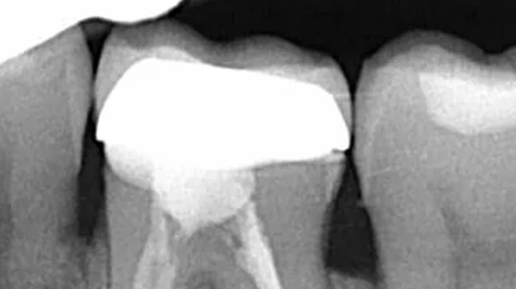

Это самый частый вопрос от пациентов, у которых на корне зуба обнаружили воспаление. И этот вопрос вполне логичный. Воспалительный очаг на верхушке корня, или в простонародье, киста, как правило, является осложнением кариеса и главной причиной потери зубов. Перед пациентом стоит выбор: удаление зуба с последующим протезированием или лечение такого зуба, но без каких-либо гарантий. По сути, выбираем между плохим или очень плохим вариантом. Коллегам сразу скажу, что я знаю, что киста- гистологический диагноз и правильнее говорить периодонтиты, очаги деструкции и т...

Сегодня мы с вами разберем одну из самых частых причин потери зубов – периодонтиты(или, как вы иногда их называете, «кисты», хотя это совсем про другое), то есть воспаление связки, в которой сидит зуб. Про строение зуба можно почитать тут. Основных причин воспалений этой связки, как правило, три. 1 . Инфекция, как осложнение кариеса. Помним нашу горную деревушку из главы 48? Сага о стоматологии. Глава 48. Что делать если сильно болит зуб ночью? Когда кариозная полость доходит до нерва, то инфекция начинает его убивать...